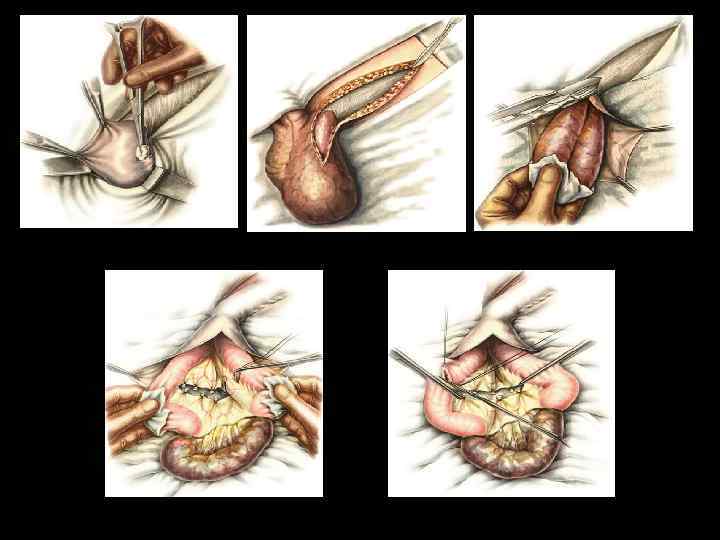

ЭТАПЫ ОПЕРАЦИИ ПРИ УЩЕМЛЕННОЙ ГРЫЖЕ • Рассечение кожи и подкожной клетчатки • Обнаружение дна грыжевого мешка без широкой мобилизации • Вскрытие грыжевого мешка • Фиксация ущемленного органа • Рассечение ущемляющего кольца • Оценка жизнеспособности ущемленных органов

ПРИЗНАКИ НЕЖИЗНЕСПОСОБНОСТИ КИШКИ • окраска – багровый или черный цвет • отсутствие пульсации краевых сосудов брыжейки • отсутствие перистальтики